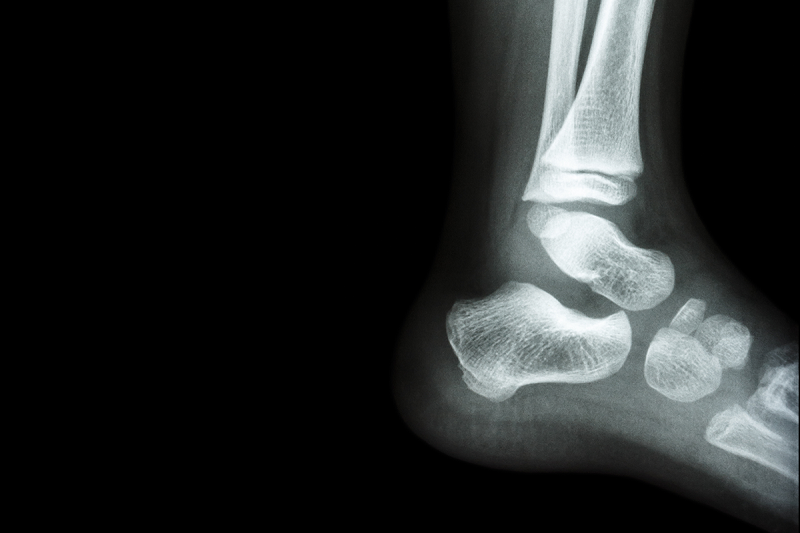

With the warmer weather upon us, we can expect an increase in paediatric ankle injuries coming to emergency departments. However, the vast majority are low-risk, soft-tissue injuries (i.e., sprains), or clinically minor fractures that have been shown to heal without specific intervention or orthopaedic follow-up. A common approach to investigating ankle injuries is to obtain an X-ray to look for a fracture, but new SickKids-led research shows there’s a better alternative that also uses less time and fewer resources.

The study, led by Dr. Kathy Boutis, Staff Emergency Physician and Senior Associate Scientist at SickKids, shows that by applying the Low Risk Ankle Rule (LRAR), X-rays could be reduced by as much as 60 per cent without missing any significant injuries. LRAR also shows that most simple ankle fractures can be managed very similarly to ankle injuries without fractures, such as with ice, anti-inflammatory medication, compression bandages and rest.